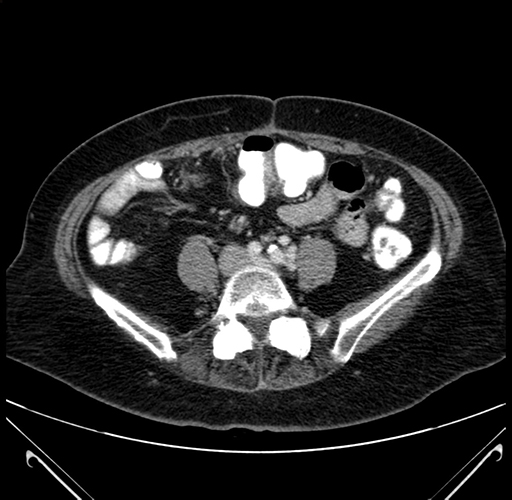

Axial Venous